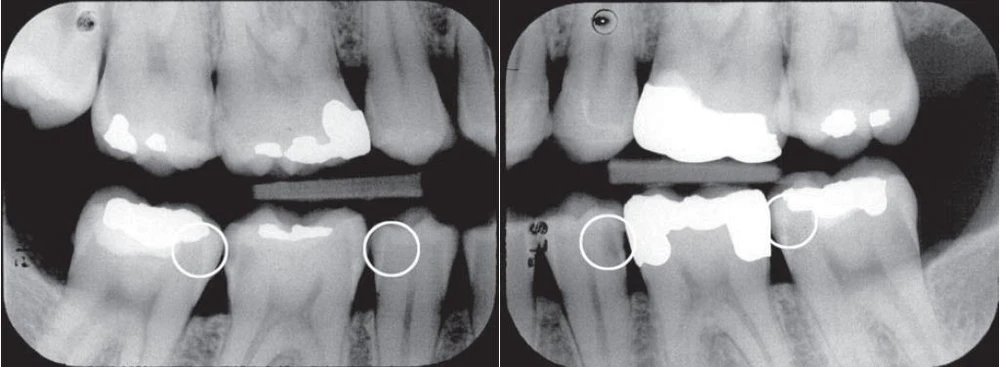

Hình 3. Phim cánh cắn phần hàm trái của bệnh nhân.

Hình 4. Phim cánh cắn ở bộ răng hỗn hợp cho thấy tổn thương sâu ngà ở mặt gần và xa răng cối sữa thứ hai và tổn thương men ở mặt gần răng cối lớn vĩnh viễn thứ nhất. Tổn thương lan rộng ở thân và chân răng cối sữa thứ nhất hàm dưới.